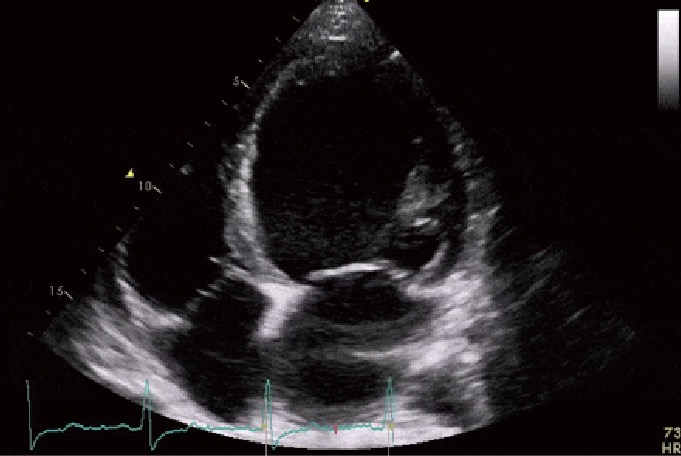

Dilated cardiomyopathy

Diagnose this pathology

4 chamber dilation, decreased systolic & diastolic function, increased volume & mass index

Describe some echo findings associated with Dilated Cardiomyopathy